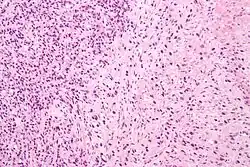

A pathologist microscopically examines the biopsy specimen for certain "Gleason" patterns. These Gleason patterns are associated with the following features:

- Pattern 1 – The cancerous prostate closely resembles normal prostate tissue. The glands are small, well-formed, and closely packed. This corresponds to a well differentiated carcinoma.

- Pattern 2 – The tissue still has well-formed glands, but they are larger and have more tissue between them, implying that the stroma has increased. This also corresponds to a moderately differentiated carcinoma.

- Pattern 3 – The tissue still has recognizable glands, but the cells are darker. At high magnification, some of these cells have left the glands and are beginning to invade the surrounding tissue or having an infiltrative pattern. This corresponds to a moderately differentiated carcinoma.

- Pattern 4 – The tissue has few recognizable glands. Many cells are invading the surrounding tissue in neoplastic clumps. This corresponds to a poorly differentiated carcinoma.

- Pattern 5 – The tissue does not have any or only a few recognizable glands. There are often just sheets of cells throughout the surrounding tissue. This corresponds to an anaplastic carcinoma.

In the present form of the Gleason system, prostate cancer of Gleason patterns 1 and 2 are rarely seen. Gleason pattern 3 is by far the most common.

The Gleason grade is based on tissue architectural patterns rather than purely cytological changes. These tissue patterns are classified into 5 grades, numbered 1 though 5. Lower numbers indicate more differentiation, with pattern 5 being the least differentiated.[4][7] Differentiation is the degree to which the tissue, in this case the tumor, resembles native tissue. Greater resemblance (lower grade) is typically associated with a better prognosis.

Gleason pattern 1 is the most well-differentiated tumor pattern. It is a well-defined nodule of single/separate, closely/densely packed, back-to-back gland pattern that does not invade into adjacent healthy prostatic tissue. The glands are round to oval shaped and proportionally large, compared to Gleason pattern 3 tumors, and are approximately equal in size and shape to one another.[4][7]

Gleason 2 is fairly well-circumscribed nodules of single, separate glands. However, the glands are looser in arrangement and not as uniform as in pattern 1. Minimal invasion by neoplastic glands into the surrounding healthy prostate tissue may be seen. Similar to Gleason 1, the glands are usually larger than those of Gleason 3 patterns, and are round to oval in shape. Thus the main difference between Gleason 1 and 2 is the density of packing of the glands seen; invasion is possible in Gleason 2, but by definition not in Gleason 1.[4][7]

Gleason 3 is a clearly infiltrative neoplasm, with extension into adjacent healthy prostate tissue. The glands alternate in size and shape, and are often long/angular. They are usually small/micro-glandular in comparison to Gleason 1 or 2 grades. However, some may be medium to large in size. The small glands of Gleason 3, in comparison to the small and poorly defined glands of pattern 4, are distinct glandular units. Mentally you could draw a circle around each of the glandular units in Gleason 3.[4][7]

Gleason pattern 4 glands are no longer single/separated glands like those seen in patterns 1–3. They look fused together, difficult to distinguish, with rare lumen formation vs Gleason 1–3 which usually all have open lumens (spaces) within the glands, or can be cribriform-(resembling the cribriform plate/similar to a sieve: an item with many perforations). Fused glands are chains, nests, or groups of glands that are no longer entirely separated by stroma-(connective tissue that normally separates individual glands in this case). Fused glands contain occasional stroma giving the appearance of "partial" separation of the glands. Due to this partial separation, fused glands sometimes have a scalloped (think looking at a slice of bread with bite taken out of it) appearance at their edges.[4][7]

Neoplasms have no glandular differentiation (thus not resembling normal prostate tissue at all). It is composed of sheets (groups of cells almost planar in appearance (like the top of a box), solid cords (group of cells in a rope like fashion running through other tissue/cell patterns seen), or individual cells. You should not see round glands with lumenal spaces that can be seen in the other types that resemble more the normal prostate gland appearance.[4][7]